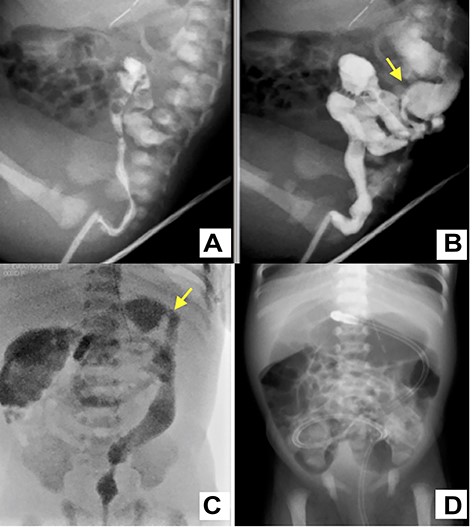

A female infant was born at 38 weeks of gestation by cesarean section. Birth weight was 3002 g and height was 49 cm. During antenatal period, the mother had gestational diabetes requiring insulin therapy from 12 weeks of gestation. The postnatal course was good, insulin treatment was discontinued and she was discharged 6 days after delivery. The baby was admitted to the neonatal unit for respiratory distress, which required respiratory management with directional positive airway pressure. Abdominal distension was observed from 8 h after birth, and the amount of milk-like gastric residue increased. The passage of meconium was confirmed by glycerin enema, but abdominal distension persisted. An abdominal X-ray showed dilated bowel loops and absent rectal gas. Therefore, intermittent continuous gastric suction was started. Contrast enema revealed a small caliber of the left colon up to the splenic flexure at 3 days of age (Fig. 1A–C.). A transanal tube was inserted into the transverse colon to initiate intestinal decompression. Subsequently, the abdominal distension was improved, and the amount of feeding could increase; intermittent intragastric continuous suction was ceased at 7 days. The next day, she had a recurrence of abdominal distension with accidental occlusion of the transanal tube (Fig. 1D). Although the symptom was improved by releasing the tube blockage, colostomy was performed because tube management at home could cause the same issue.

A water-soluble contrast enema image shows characteristic narrowing of the left colon up to the splenic flexure (yellow arrow) (A–C); a transanal tube was inserted into the transverse colon (C); the plain abdominal X-ray of the occluded tube shows dilation of the colon from the transverse colon to the oral side (D).